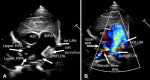

Partial Anomalous Left Pulmonary Artery: Pseudo-Pulmonary Sling